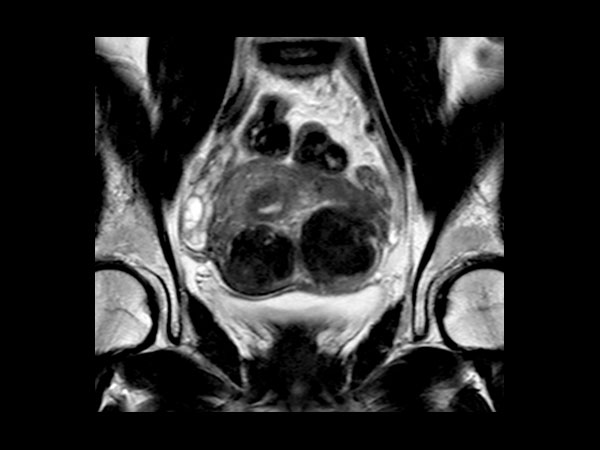

Female Pelvis

Toyonaka Hospital, Japan